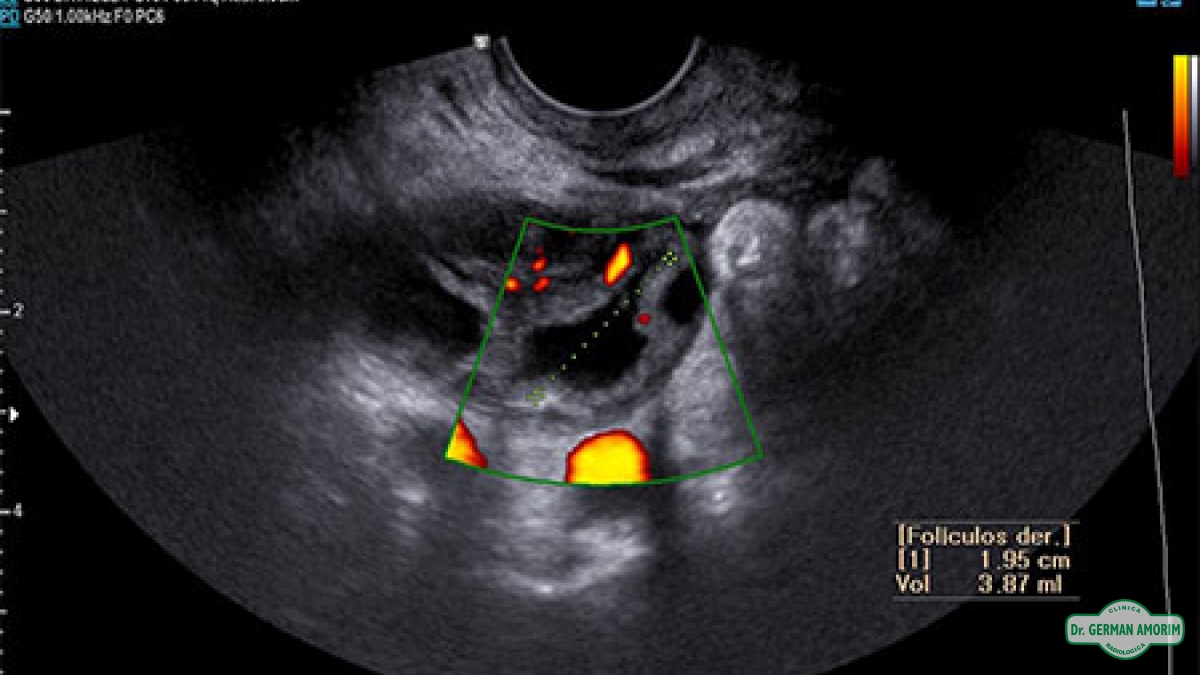

Ovarios: se observa la cantidad de folículos de cada ovario y el crecimiento de los mismos. Cada folículo del ovario va creciendo a lo largo del ciclo, hasta romper ( 19 a 23mm.) al momento de la ovulación y expulsar el o los óvulos.

Ecográficamente, si se produce la ovulación se visualizan signos directos de la misma, que sería la desaparición del folículo o el aplanamiento e irregularidades de la pared del mismo y signos indirectos como la presencia de líquido en el fondo de saco de Douglas.